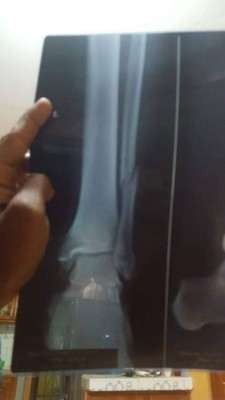

Según los informes médicos se trata de una fractura en el peroné de la pierna izquierda, la cual se rompió tras un encontronazo con 'Buba' López en el tramo final del encuentro.